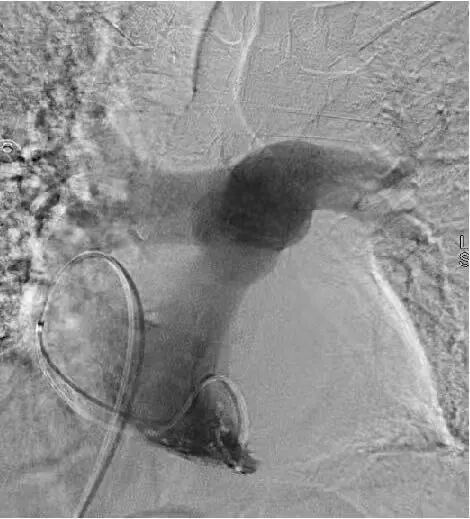

最后通过肺动脉造影,精准实施取栓、碎栓操作。

整个手术仅用一个半小时便顺利完成,血栓被彻底清除。术后效果立竿见影,小李的胸闷、憋气症状明显缓解,咳嗽咳痰好转,右下肢疼痛也有所减轻。